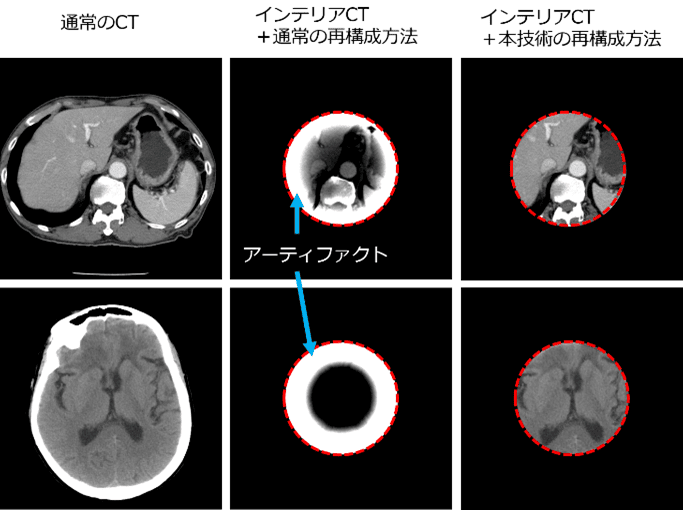

ヒトの胴体と脳に対しインテリアCT測定を行ったのち、従来方法と本技術の方法でCT画像を再構成した。その結果、従来方法ではアーティファクト(誤差)のためほとんどの情報が欠落したが(右図中央)、本技術の方法では、通常のCT画像と遜色ない高精度のインテリアCT画像が取得できた(右図右側)。この際のX線被曝量は通常のCTに比べて1/4~1/8に相当する。